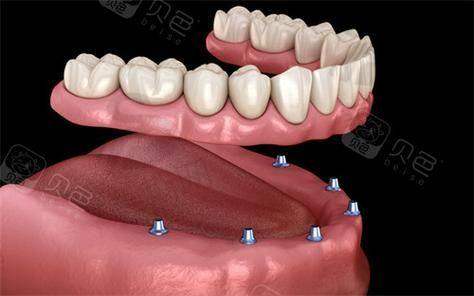

1. 牙齿种植中 心:开展即刻种植、即刻负重、全口/半口种植修复、骨增量技术(GBR/Onlay植骨)、上颌窦内外提升等,尤其擅长高龄患者复杂条件种植,采用“数字化导板 + 微创种植”技术,实现术后24小时正常进食。

即刻负重技术:针对单颗牙缺失患者,采用“微创拔牙 + 即刻种植 + 临时冠修复”一体化流程,拔牙后立即植入种植体并安装临时牙冠,实现“当天种牙当天用”。对于半口/全口缺失患者,采用“All - on - 4/6”即刻负重技术,仅需植入4 - 6颗种植体即可修复半口牙齿功能,术后48小时可正常咀嚼软食,3个月完成更终修复。

3. 哈尔滨优诺博士口腔半口All - on - 4即刻负重种植:88000元(含6颗种植体 + 桥架)